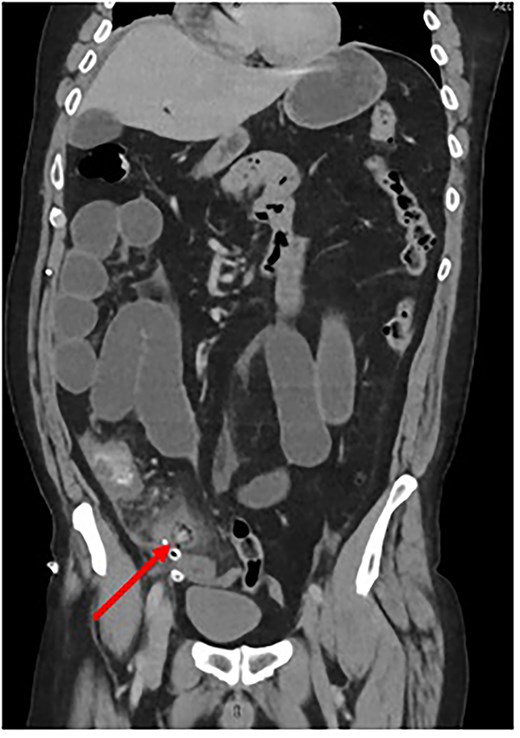

In the postoperative period, the patient developed an ileus. To exclude a mechanical cause of bowel obstruction, a contrast-enhanced CT abdomen-pelvis was performed. This confirmed an ileus but also reported a ‘Persisting blind ending tubular structure extending from caecum inferior and medially’ and “intraluminal free gas consistent with necrosis” (Fig. 1). Conclusion by the radiologist stated that appearances were consistent with “ongoing appendicitis.”

Coronal CT scan depicting Surgicel® as a tubular structure containing gas. (Created by authors)

The decision was made to return to theater for completion appendicectomy. Laparoscopic surgery was unfeasible due to gross bowel dilatation, and so a lower midline laparotomy was performed. The intraoperative findings confirmed a resected appendix with Surgicel® in the surgical bed.